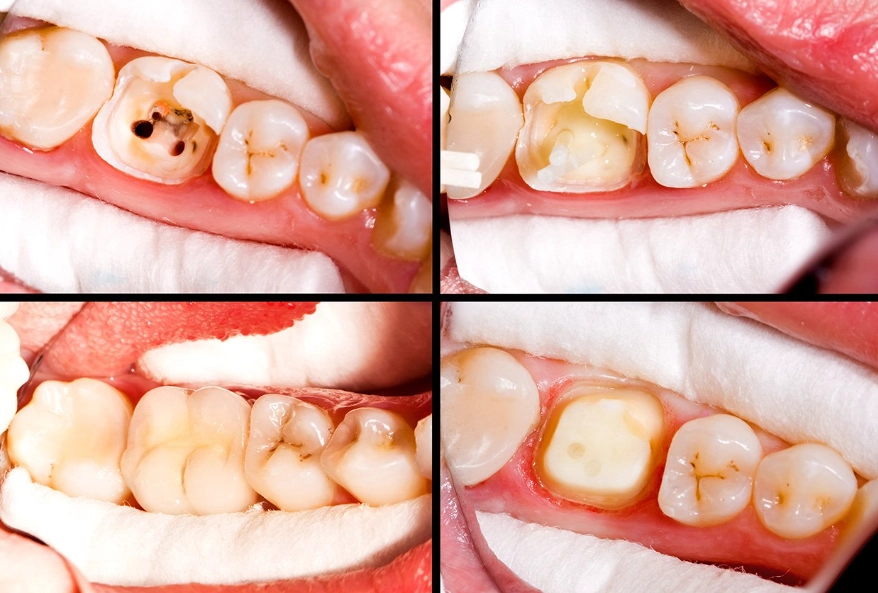

At its core, a root canal treatment on a premolar is a procedure to remove infected or inflamed pulp—the soft tissue inside your tooth containing nerves and blood vessels. Once that's gone, the inside of the tooth is cleaned, disinfected, and sealed. Think of it like removing the spoiled wiring from a house and filling the space with a stable, inert material. The goal is to eliminate pain, stop the spread of infection, and allow you to keep your natural tooth structure. The alternative, pulling the tooth, creates a whole new set of problems like bone loss and shifting teeth, which are costlier and more complex to fix down the line.

Not all teeth are created equal. Premolars, also called bicuspids, are the teeth between your canines and molars. You have eight of them. Their job is a hybrid: they help with tearing food like canines and grinding it like molars. This dual role makes their anatomy a bit of a wild card.

The biggest headache with premolar root canals is their root structure. While a front tooth typically has one simple root canal, a premolar can be a surprise package.